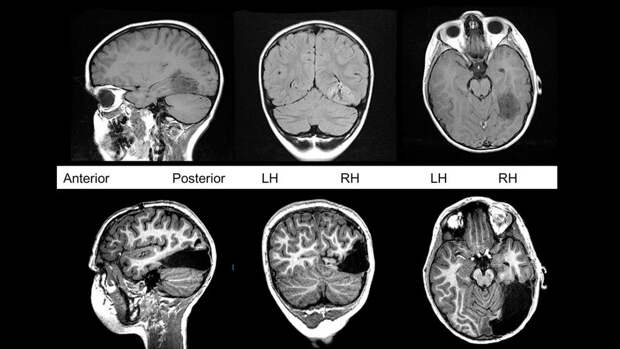

Врачи провели операцию незадолго до седьмого дня рождения Таннера. Перед операцией врачи поместили электроды на поверхность мозга мальчика и внутрь зрительной коры. На протяжении недели они изучали электрическую активность его мозга, чтобы выяснить, какая область мозга связана с судорогами и какие части придется удалить.

Затем врачи вскрыли череп мальчика и удалили опухоль вместе с прилежащими тканями - затылочной долей мозга, обеспечивающей восприятие зрительной информации, и половиной височной доли, которая участвует в образовании долговременной памяти, обрабатывает визуальную и слуховую информацию, способствует пониманию языка.

Так мальчик остался без 1/6 части мозга.

Однако сегодня, спустя пять лет, Таннер - успешный шахматист. Утраченные функции правого полушария полностью взяло на себя левое. Его необычный клинический случай, иллюстрирующий феномен нейропластичности, международная группа специалистов во главе с психологом Марлен Берманн из Университета Карнеги - Меллона в США описала в статье в журнале Cell.

С того момента, как Таннер пришел в себя после операции, врачи следили за электрической активностью его мозга. На протяжении недели, которую мальчик провел в больнице, они составили "карту" областей его мозга и выяснили, какие из них взаимодействовали друг с другом, а какие - нет.

На протяжении трех лет после операции Берманн каждые полгода проводила с Таннером серию игр на память и обучение, которая включала задания на память, распознавание и называние объектов. Во время игр она наблюдала за работой мозга мальчика с помощью МРТ. Это позволило изучить, как кровь приливает к различным частям его мозга во время их повышенной активности, и выяснить, как результаты Таннера отличаются от результатов его ровесников с целым мозгом.